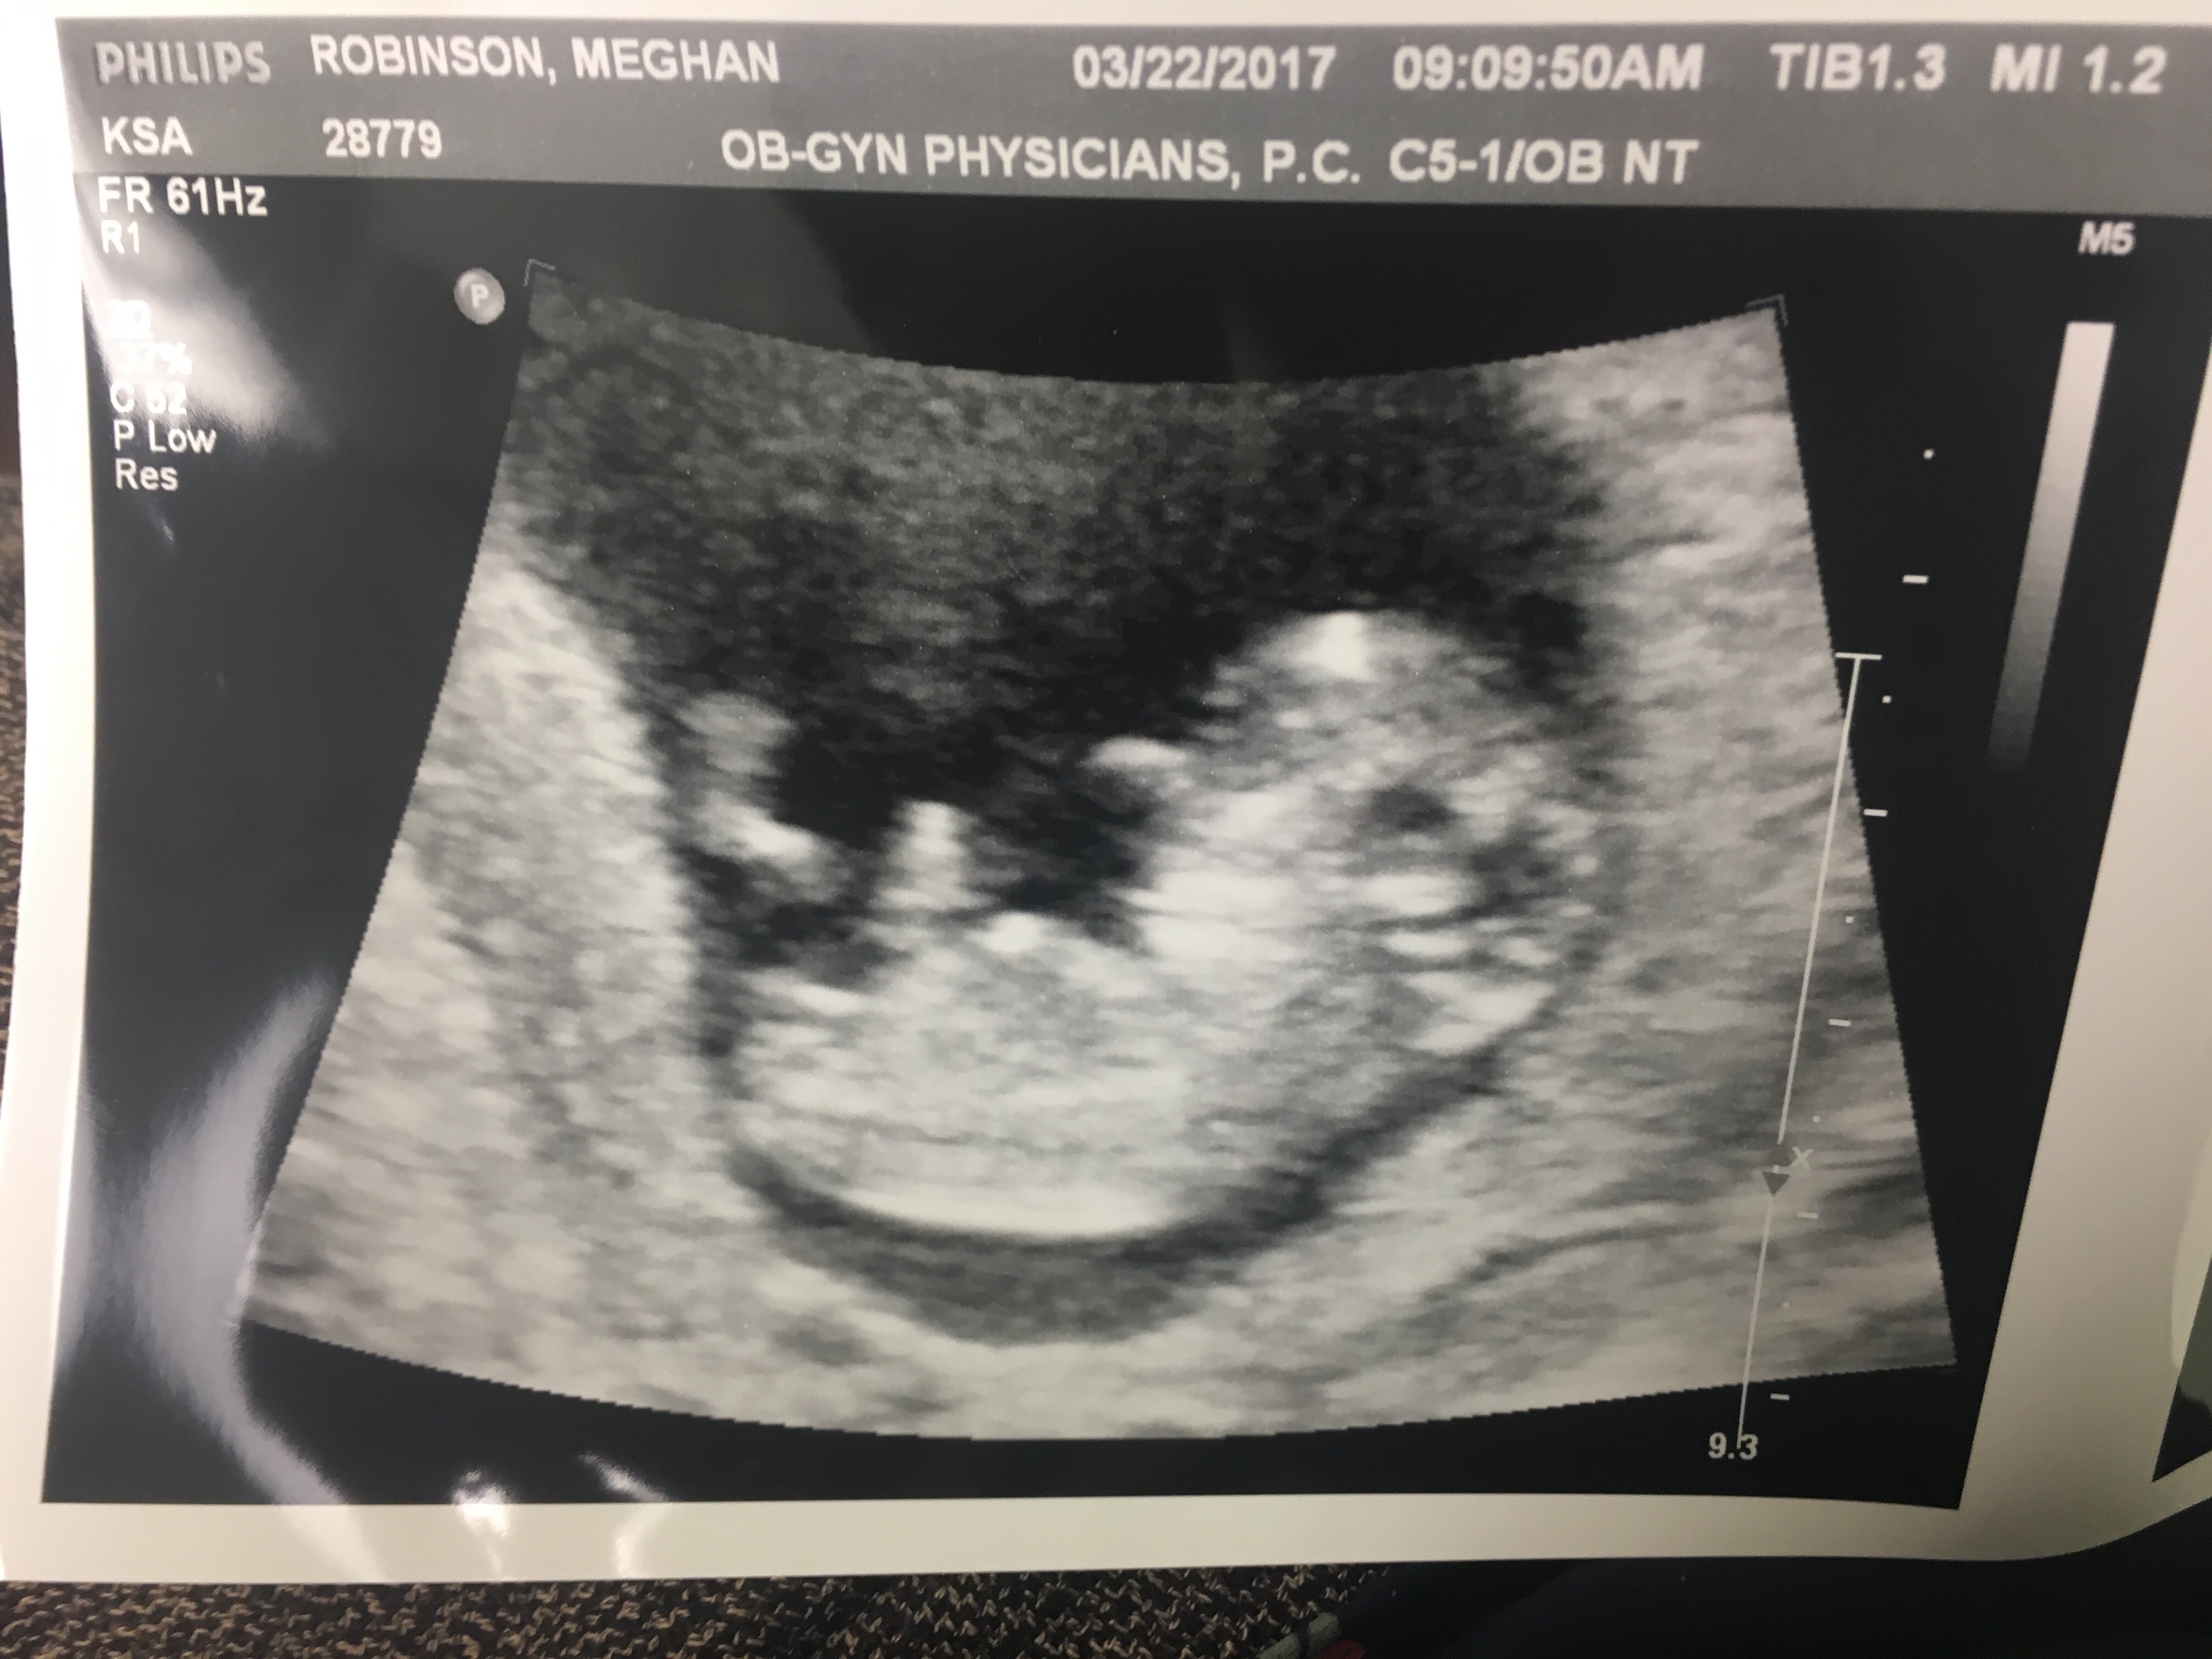

We have our ultrasound to find out the gender on Wednesday, but curious to see if anyone has any guesses before then!!

this was 11.5 weeks along! the dark thick line pointing upward next to the leg is the umbilical cord. the ultrasound tech confirmed that but i thought i should clarify just in case lol!

Too early to make an accurate guess- not girls and boys look the same at this gestation. That being said, the nub does look girlie but it's very early still and can rise.

Too early, although nub looks like it might be rising. Still 50/50 though.